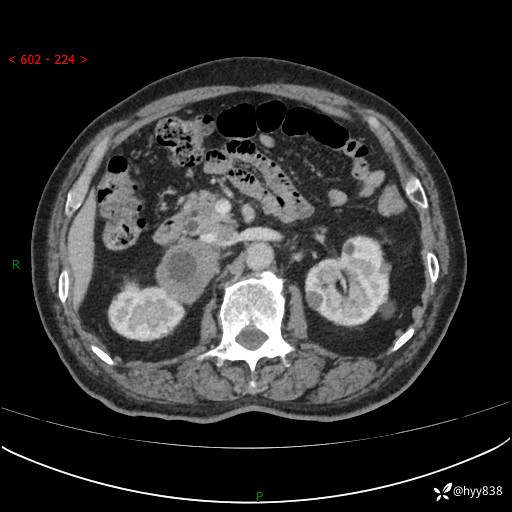

【患者信息】:76岁/男

【主诉】:检查发现右侧肾上腺占位6天

【现病史及既往史】:患者6天前体检发现右侧肾上腺占位,无腰痛,无放射痛,无尿频、尿急、尿痛及肉眼血尿,无畏寒、发热,无恶心、呕吐,今为求进一步治疗,遂来我院就诊,门诊拟“右侧肾上腺占位”收住入院。 起病以来,患者精神、饮食、睡眠可,大小便如常,体力体重无明显变化。

【检查】:肾上腺CT平扫+增强